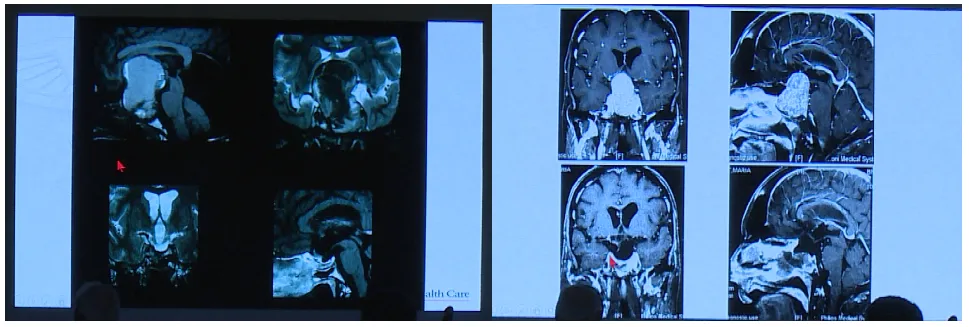

Couldwell教授演讲中展示部分巨大垂体瘤病例。目前巨大垂体瘤主要治疗方式为手术,目的在于最大程度切除肿瘤、改善神经功能障碍以及保留正常垂体功能。巨大垂体腺瘤术前根据影像学表现和临床症状,个体化选择合适手术入路,是成功切除肿瘤的关键。经蝶入路、经颅入路和联合入路是切除肿瘤的可行方法。

垂体瘤通常起源于鞍内,但若肿瘤巨大向颅内突破鞍隔孔,向颅内广泛发展,包绕颅内血管(特别是大脑中动脉、大脑前动脉、大脑后动脉及其重要分支血管),这种情况下通常选择经颅入路进行肿瘤切除。经颅垂体腺瘤切除术根据肿瘤生长方向位置可分为三种入路途径:经额入路、经硬脑膜外入路和经翼点入路。

对于单纯经颅入路,Couldwell教授总结了其优势与劣势。优势包括手术视野大、病灶暴露充分、操作空间较经蝶入路更大,对保护颅底重要结构具有重要意义,可移除鞍上神经释放视神经;劣势包括鞍内区域远距离可视化困难、需要脑组织收缩。

针对巨大垂体瘤何时需要开颅手术,Couldwell教授提出经颅入路适应症如下:经颅途径仍用于切除1%-4%的垂体大腺瘤;经蝶入路的直接可视化和可及性受限;鞍膈肌收缩;鞍旁延伸或不可触及的鞍上延伸远离中线;纤维致密性肿瘤伴大鞍上延伸;活动性鼻窦感染;邻近动脉瘤患者;扩张的鞍内颈动脉;脑组织侵犯;海绵窦侵犯引起的病变。